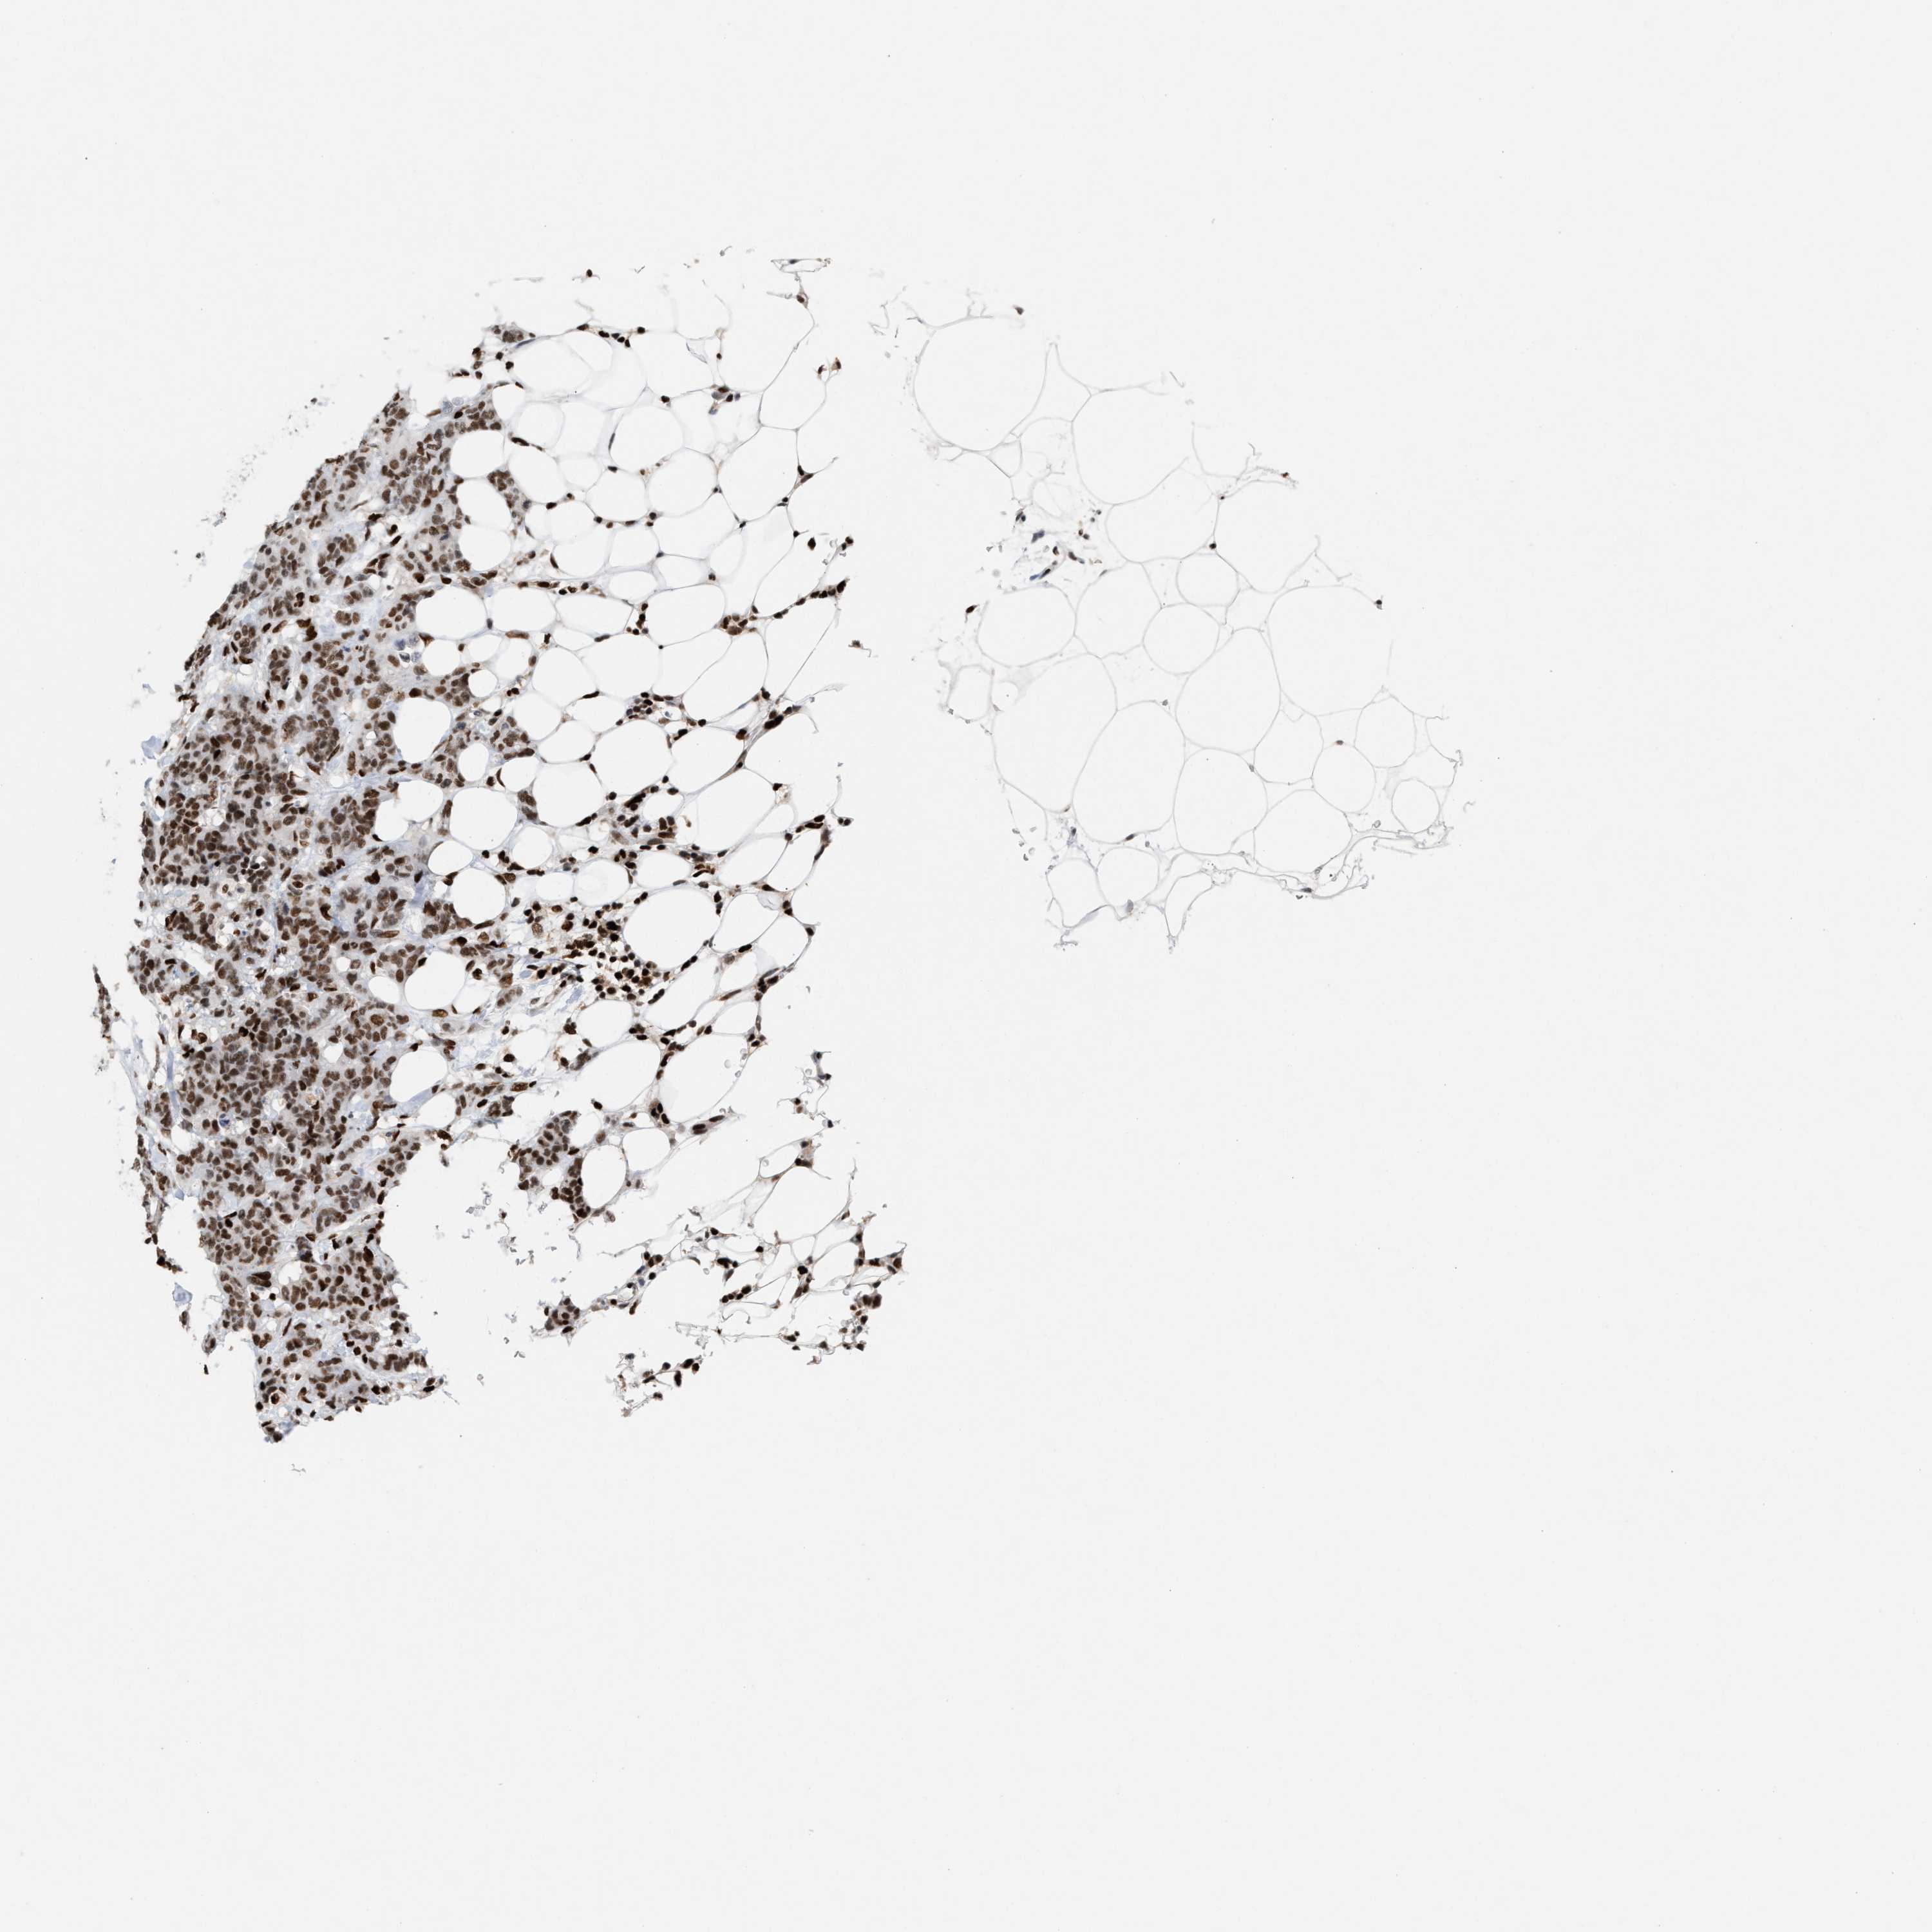

CANCER BREAST CANCER Show tissue menu

BRCA TCGA BRCA VALIDATION PROTEIN EXPRESSION

ANTIBODIES

AND

VALIDATION